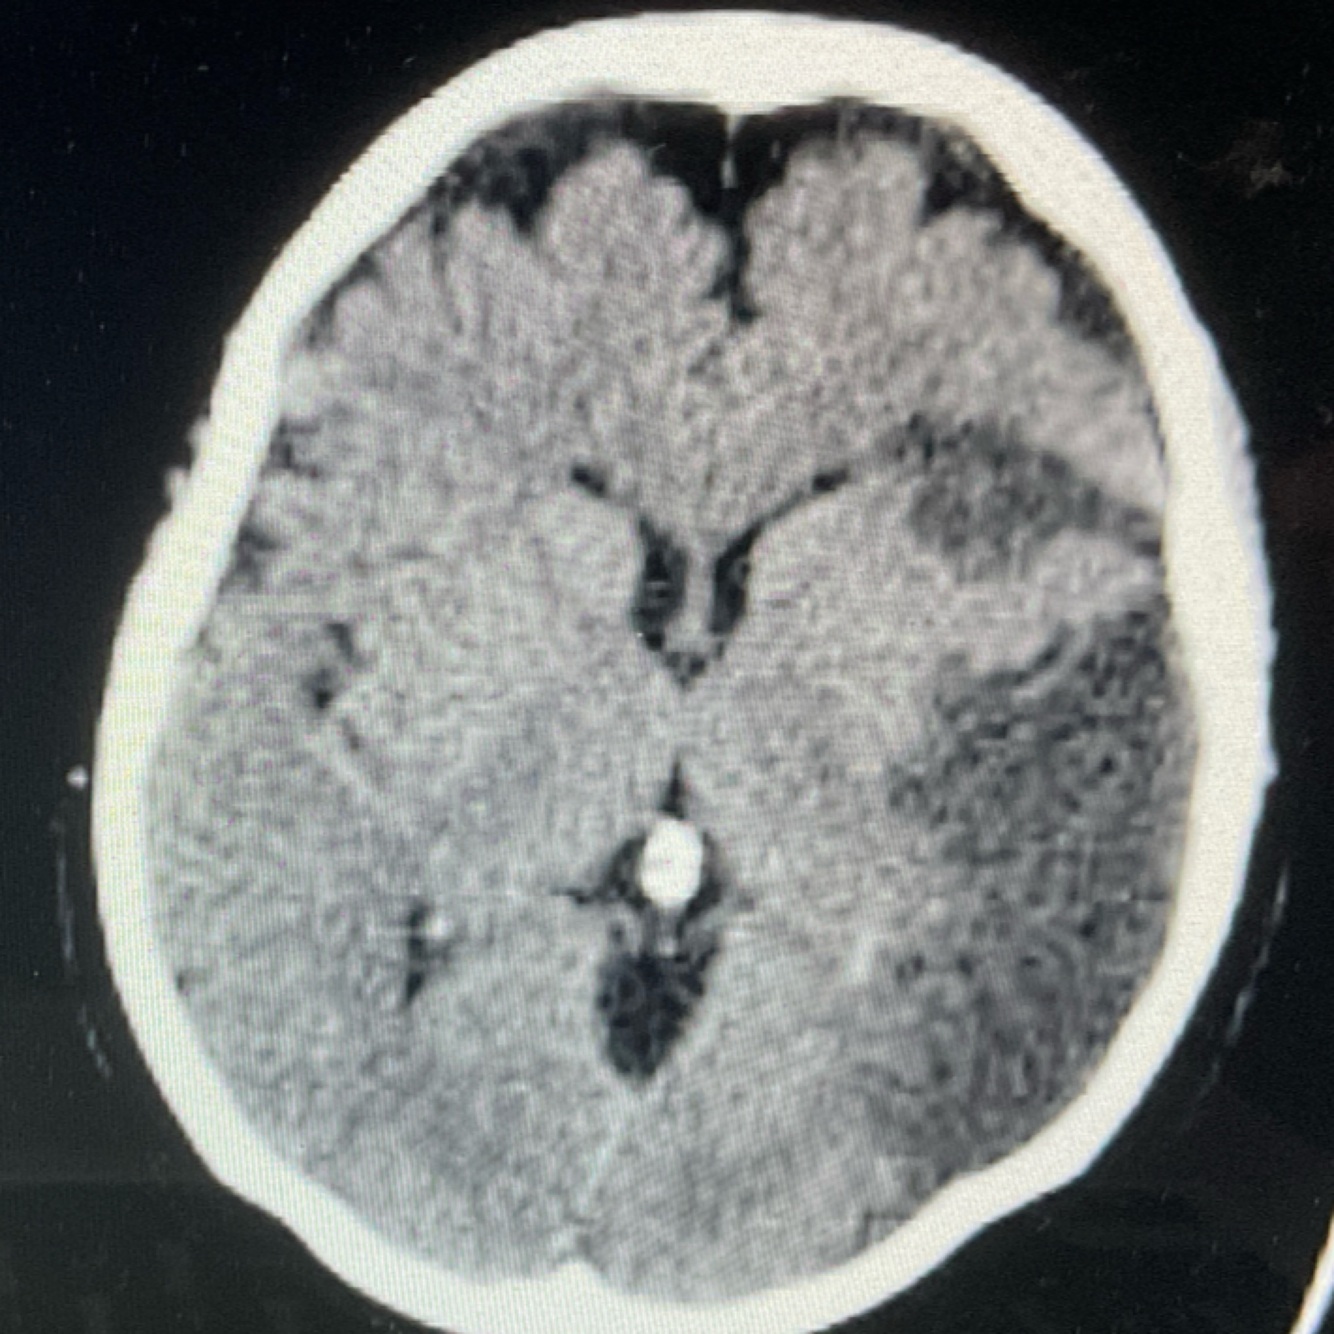

A

EVC isquémico subagudo